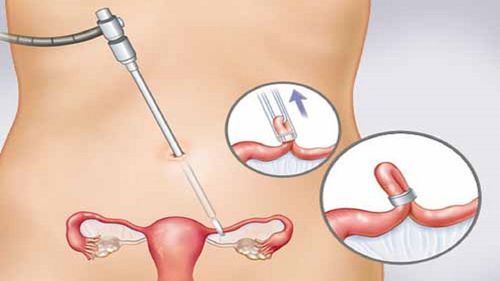

- Nội soi ổ bụng: Phương pháp này cho phép các bác sĩ chẩn đoán và điều trị lạc nội mạc tử cung bằng cách sử dụng một dụng cụ có gắn máy quay phim. Bác sĩ đưa dụng cụ có đèn chiếu sáng vào cơ thể bệnh nhân, cùng với một ống kính để quan sát bên trong vùng xương chậu và tìm ra lạc nội mạc tử cung. Hình ảnh thu được giúp bác sĩ xác định tình trạng bệnh, mức độ tổn thương, và vị trí tổn thương để đưa ra phương án điều trị thích hợp.

- Chẩn đoán bằng nội soi: Trong quá trình này, bác sĩ bơm khí vào ổ bụng và rạch một vết nhỏ để nội soi. Qua ống nội soi, bác sĩ có thể quan sát toàn bộ ổ bụng. Đây là cách chẩn đoán tình trạng lạc nội mạc tử cung đáng tin cậy nhất. Bác sĩ có thể lấy mẫu mô nhỏ để kiểm tra xem có tế bào ung thư hay không. Trong suốt quá trình thực hiện, bác sĩ sẽ gây mê toàn thân cho bệnh nhân.

- Phẫu thuật nội soi: Nếu phát hiện có dấu hiệu lạc nội mạc tử cung, bác sĩ sẽ tiến hành phẫu thuật loại bỏ các mô lạc nội mạc tử cung khi nội soi. Các khối u được cắt bỏ, đốt bằng laser hoặc các kỹ thuật khác.